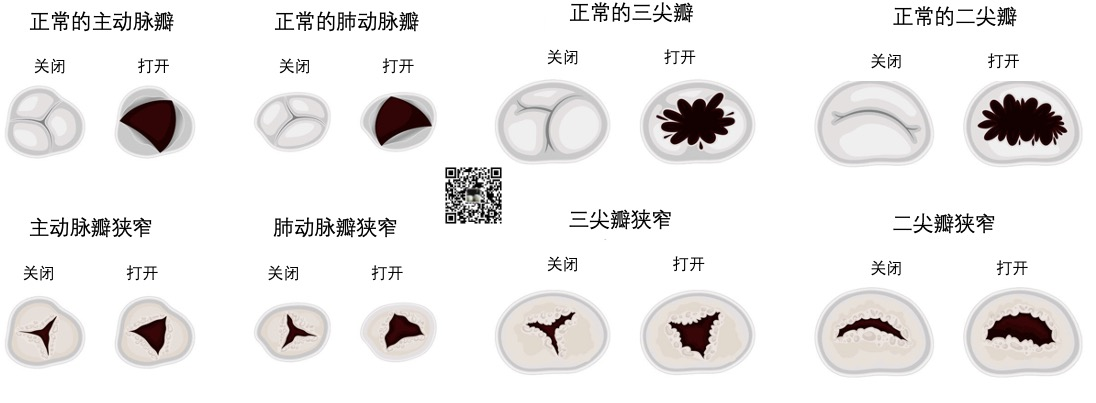

心脏瓣膜病(valvular heart disease)

最常见的心脏瓣膜狭窄如下图所示:

心脏瓣膜狭窄是指狭窄的瓣膜无法像正常瓣膜一样打开,使血流畅通。

随着时间的推移,这会损伤过度劳累的心肌。

最常见的主动脉瓣狭窄(Aortic Valve Stenosis)会使左心室泵血更加困难,血液无法通过瓣膜流出体外。

在肺动脉狭窄(Pulmonary Valve Stenosis)的患者中,当右心室试图将血液从肺动脉瓣泵出时,心室内的压力就会比正常情况下高得多。这时,心脏必须更加努力地将血液泵入肺部动脉。